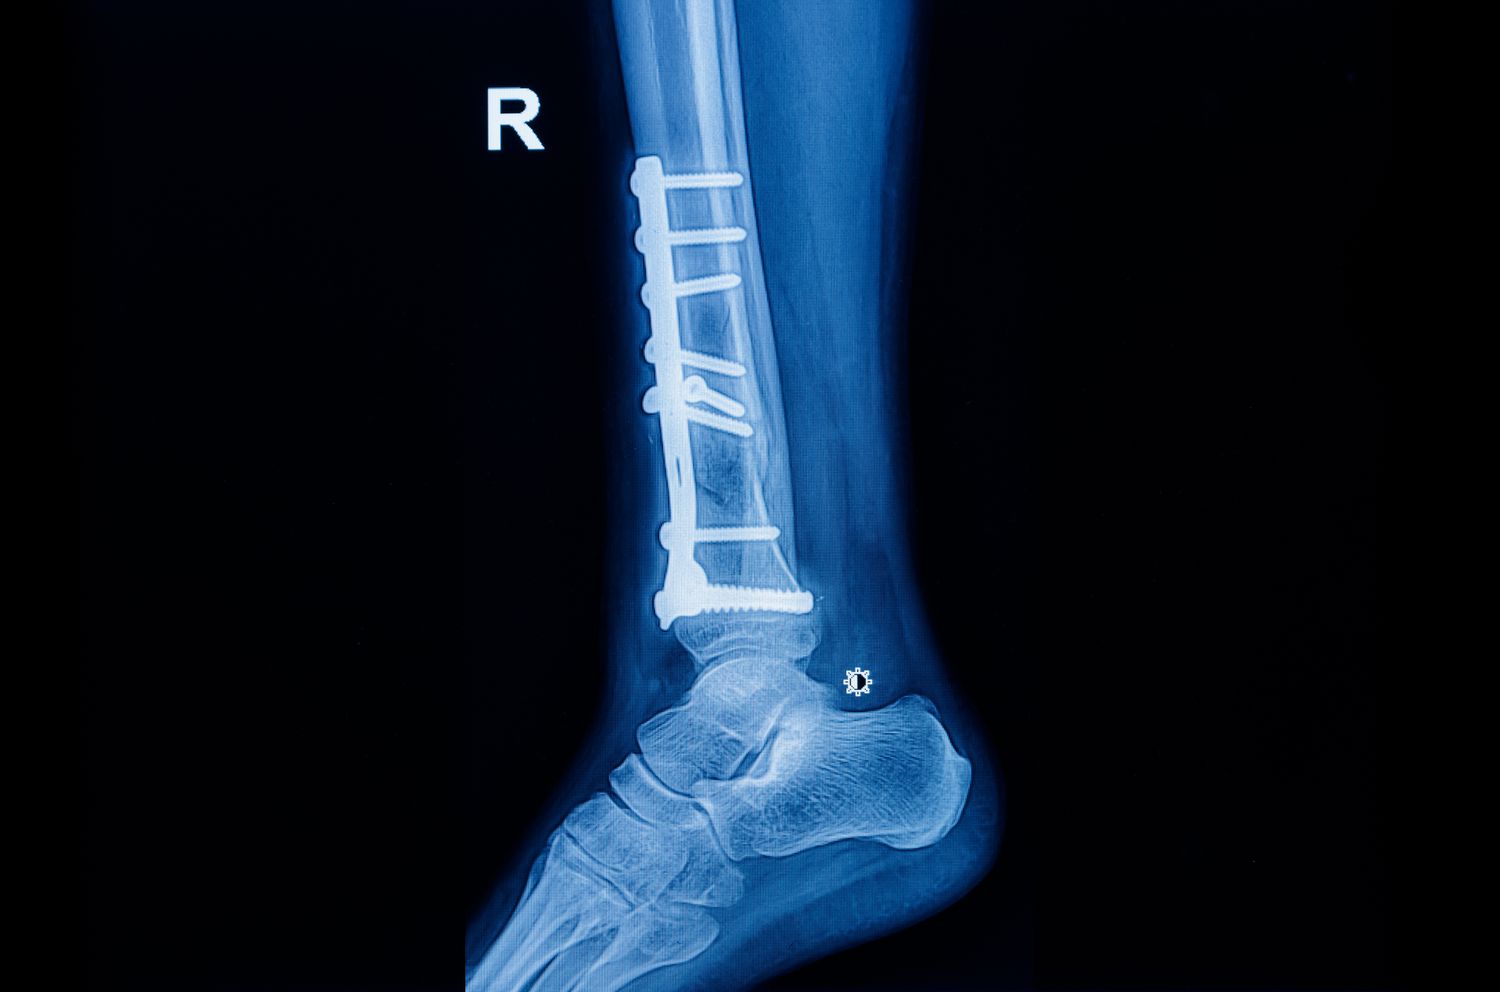

Over the next few months, the patient attended regular follow-ups. By December, the fracture site had aligned well and X-rays showed proper healing. But by the end of that month, one image revealed a slight bend in the implant. The patient claimed it was due to faulty fixation or poor-quality material, and alleged that the doctors suppressed the problem. He later underwent further care at another hospital, and approached the consumer forum demanding compensation for medical negligence.

The hospital argued that the implant failure was a known complication, not an error. The treating team had followed standard orthopaedic protocols, and there was no evidence of infection, mishandling, or deviation from accepted medical practice. The second surgeon who treated the patient later confirmed this in his testimony — saying that the initial surgery was appropriate, the failure occurred because of delayed bone union, and that the bones had eventually healed without any fresh operation.

The Kerala State Commission agreed. It observed that the failure occurred nearly five months after fixation, by which time the patient was already mobile. It accepted the expert’s opinion that such implant stress is possible in compound fractures and doesn’t imply defective equipment or poor surgery. The earlier order of negligence was set aside, and the doctors were cleared.